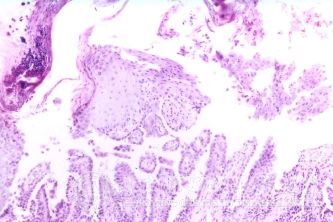

北京京城皮肤医院指出,老年瘙痒症的症状:老年瘙痒症发生于老年人,往往以躯干较痒;冬季瘙痒症出现于寒冷的季节由于寒冷而诱发,病人常在脱身睡觉时开始感觉股前侧内侧小腿等部位剧烈瘙痒,越抓越痒而越痒越抓,直至局部出血为止。